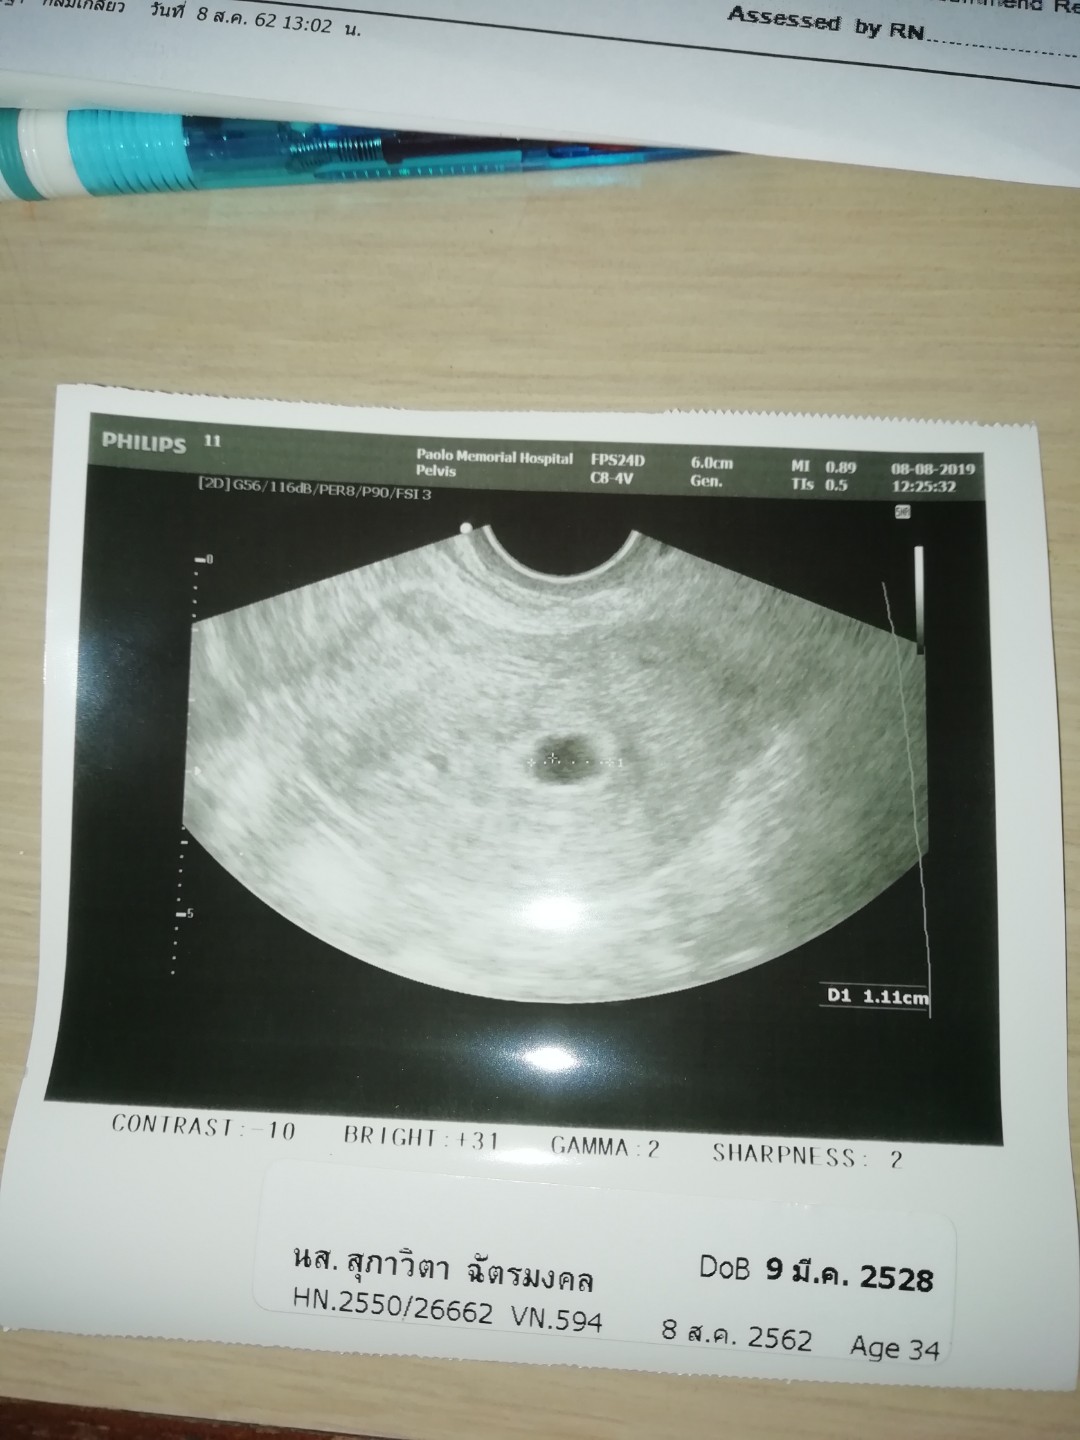

ซาวตอน 6 สัปดาห์ก็ไม่เห็นเด็กค่ะ ซาวอีกครั้ง 8 สัปดาห์เจอเลยค่ะ

ไม่ต้องกังวลค่ะ เราก็เจอแบบนี้ตอน 6w เจอตัวเด็กตอน8w